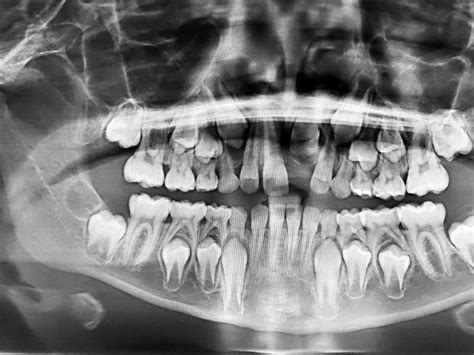

El paciente manifestó que hacía mucho había sufrido un trauma en los dientes 8 y 9, que le habían realizado 2 endodoncias, que luego con el tiempo las coronas cambiaron de color y finalmente se le fracturaron (fig. 1). Se evaluó la condición local y general de los tejidos blandos y duros para la posible colocación de implantes dentales inmediatos como reemplazo de los dientes 8 y 9. También se realizaron coronas provisionales de acrílico para la fase de diagnóstico. En la radiografía periapical se observan los restos radiculares con tratamientos endodónticos previos y lesiones periapicales.

Figura 2. Radiografía inicial.

Además de las radiografías convencionales se le indicó una tomografía axial computarizada con la cual se planificó la posición, inclinación y viabilidad de la colocación de los implantes. La confirmación de las distancias horizontales entre implante e implante, entre los implantes y dientes adyacentes y el remanente apical de hueso fueron también registradas con la tomografía axial computarizada.